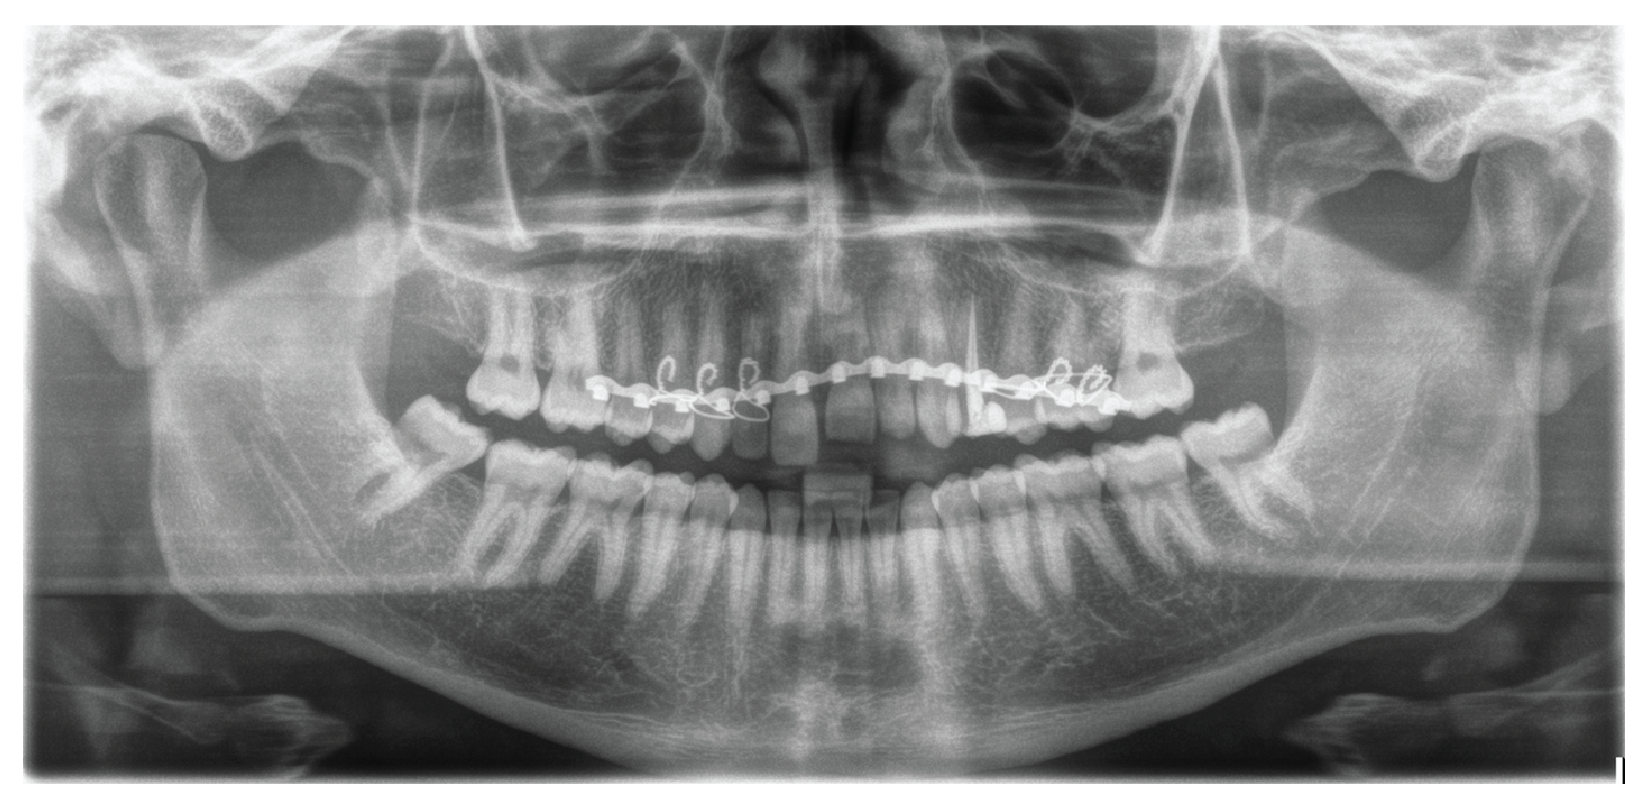

III. Panoramic Radiograph Analysis

Post-treatment panoramic radiograph (Figure 7) shows proper root alignment with no further root resorption of the maxillary left central and lateral incisors. The maxillary left lateral incisor underwent root canal treatment and received a permanent restoration.

Figure 7: Post-treatment panoramic radiograph. Panoramic radiograph at the end of treatment showed proper root alignment with no further root resorption of the maxillary left central and lateral incisors. The maxillary left lateral incisor underwent root canal treatment and received a permanent restoration.